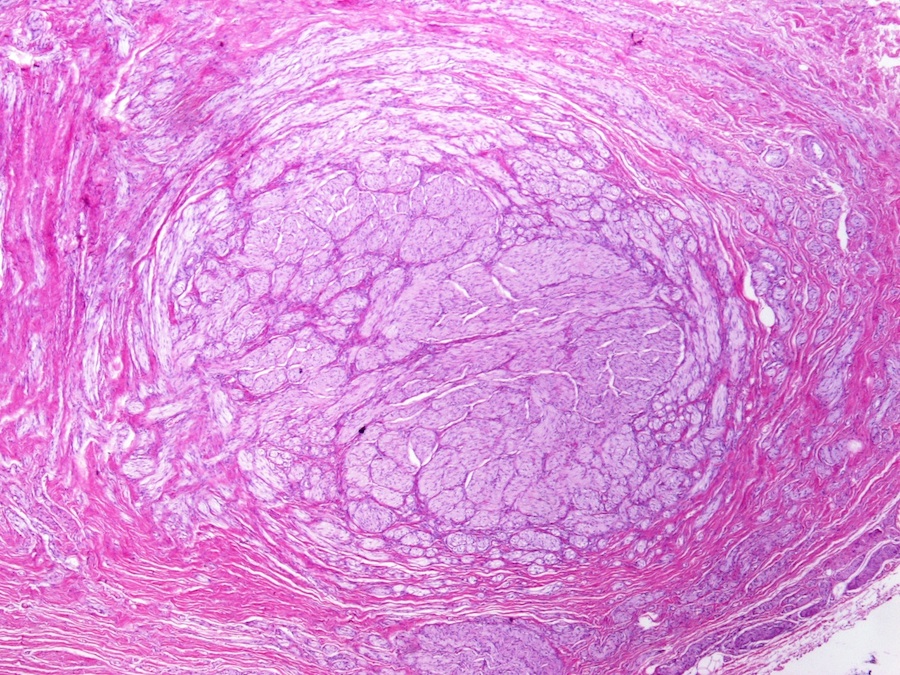

Microscopic images:

Microscopic images:

Immunostain images:

Both cases showed disorganized and thickened nerve bundles composed of spindle shaped cells, without atypia. Case A also showed a focal foreign body type giant cell reaction adjacent to the disorganized nerve bundles and a strongly immunoreactive S100 stain.

Histology typically shows hyperplastic nerve bundles, positive for S100.

Immunostain images:

Both cases showed disorganized and thickened nerve bundles composed of spindle shaped cells, without atypia. Case A also showed a focal foreign body type giant cell reaction adjacent to the disorganized nerve bundles and a strongly immunoreactive S100 stain.

Histology typically shows hyperplastic nerve bundles, positive for S100.